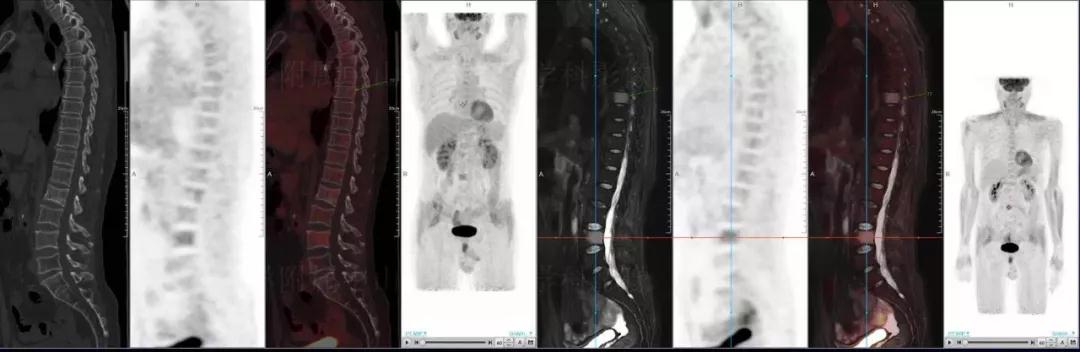

中山醫(yī)院核醫(yī)學(xué)科基于聯(lián)影“時(shí)空一體”超清TOF PET/MR的融合顯像優(yōu)勢(shì),進(jìn)行了大量的臨床掃描,發(fā)現(xiàn)多例由MGUS向多發(fā)性骨髓瘤轉(zhuǎn)變,并從中總結(jié)出了一定的共同征象,未來可能實(shí)現(xiàn)多發(fā)性骨髓瘤的早期篩查。此外,PET/MR在多發(fā)性骨髓瘤的療效評(píng)估方面,也存在顯著優(yōu)勢(shì)。

(男性,53歲。確診多發(fā)性骨髓瘤10月。經(jīng)過7周期VCD方案化療后,現(xiàn)行療效評(píng)價(jià)。)